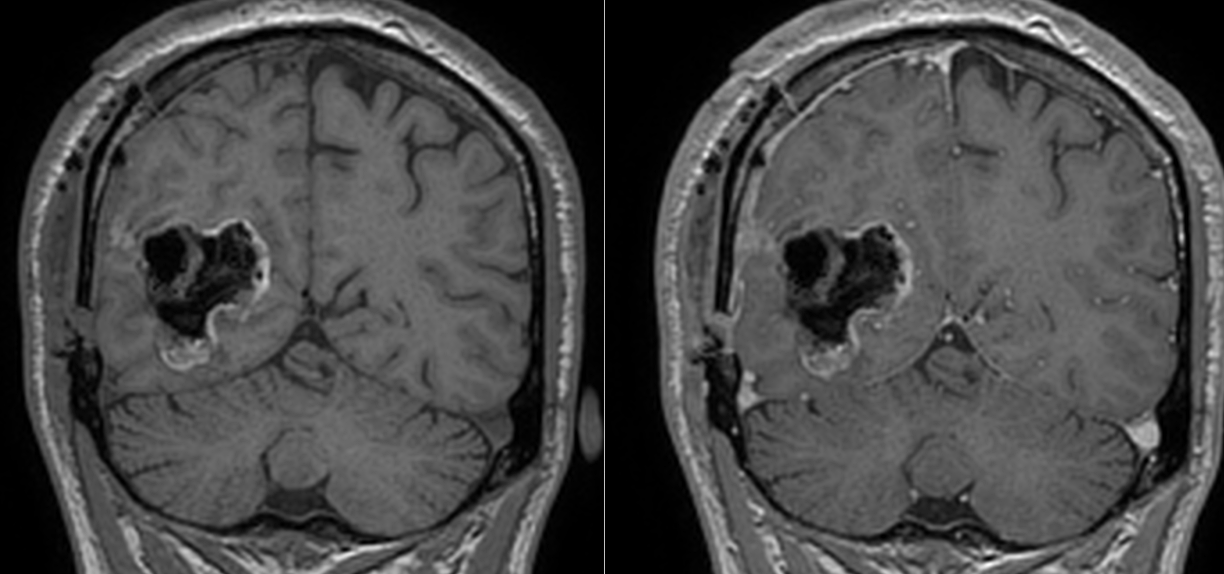

Investigația prin RMN cerebral a clarificat situația: exista o tumoră cerebrală situată în regiunea occipito-temporală dreaptă, o zonă a creierului implicată în procesarea informației vizuale și în recunoașterea fețelor.

Soluția terapeutică a fost intervenția chirurgicală, cu scopul de a îndepărta tumora cât mai complet posibil, protejând în același timp funcțiile neurologice importante din jur.

Operația a decurs în condiții bune, iar tumora a fost rezecată într-o proporție foarte mare. Analiza microscopică a confirmat diagnosticul de astrocitom anaplazic (grad III) – o tumoră glială cu potențial agresiv.